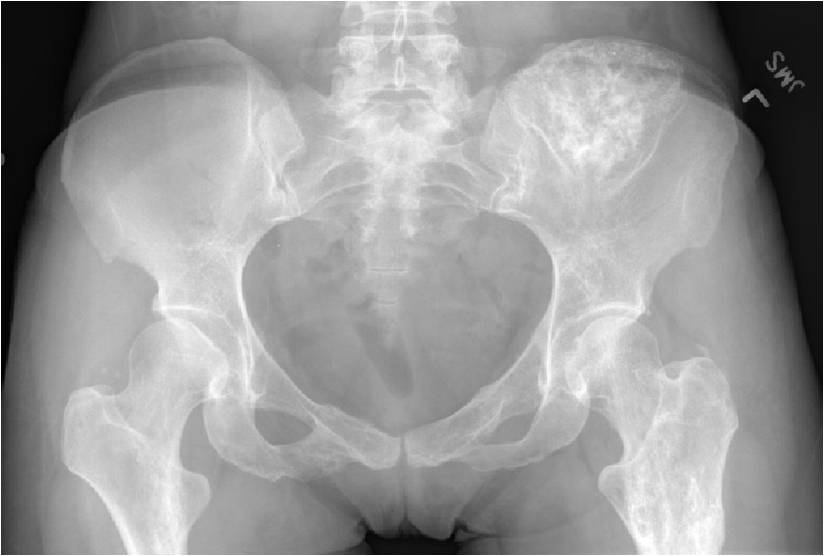

- Enchondromas of the pelvis, vertebrae and ribs are uncommon

- Almost all hyaline cartilage tumors of the pelvis are considered malignant based on anatomic location no matter what the pathology shows. These tumors will ultimately grow locally and have the potential to dedifferentiate or change into a higher grade chondrosarcoma.

- Features consistent with chondrosarcoma

- Pain attributable to lesion

- Age greater than 50

- Cortical destruction and a soft tissue mass

- Periosteal reaction and thickening

- Endosteal erosion>2/3 cortical thickness on a CT scan

- Size greater than 5 cm

- Bone Scan: Lesion that is hotter than ASIS

- The most common sites to undergo malignant change are the scapula, rib cage and pelvis